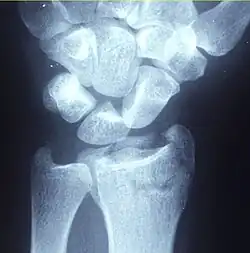

| Other names | Broken wrist[1] |

| A Colles fracture as seen on X-ray: It is a type of distal radius fracture. | |

A distal radius fracture, also known as wrist fracture, is a break of the part of the radius bone which is close to the wrist.[1] Symptoms include pain, bruising, and rapid-onset swelling.[1] The ulna bone may also be broken.[1]

In younger people, these fractures typically occur during sports or a motor vehicle collision.[2] In older people, the most common cause is falling on an outstretched hand.[2] Specific types include Colles, Smith, Barton, and Chauffeur's fractures.[2] The diagnosis is generally suspected based on symptoms and confirmed with X-rays.[1]